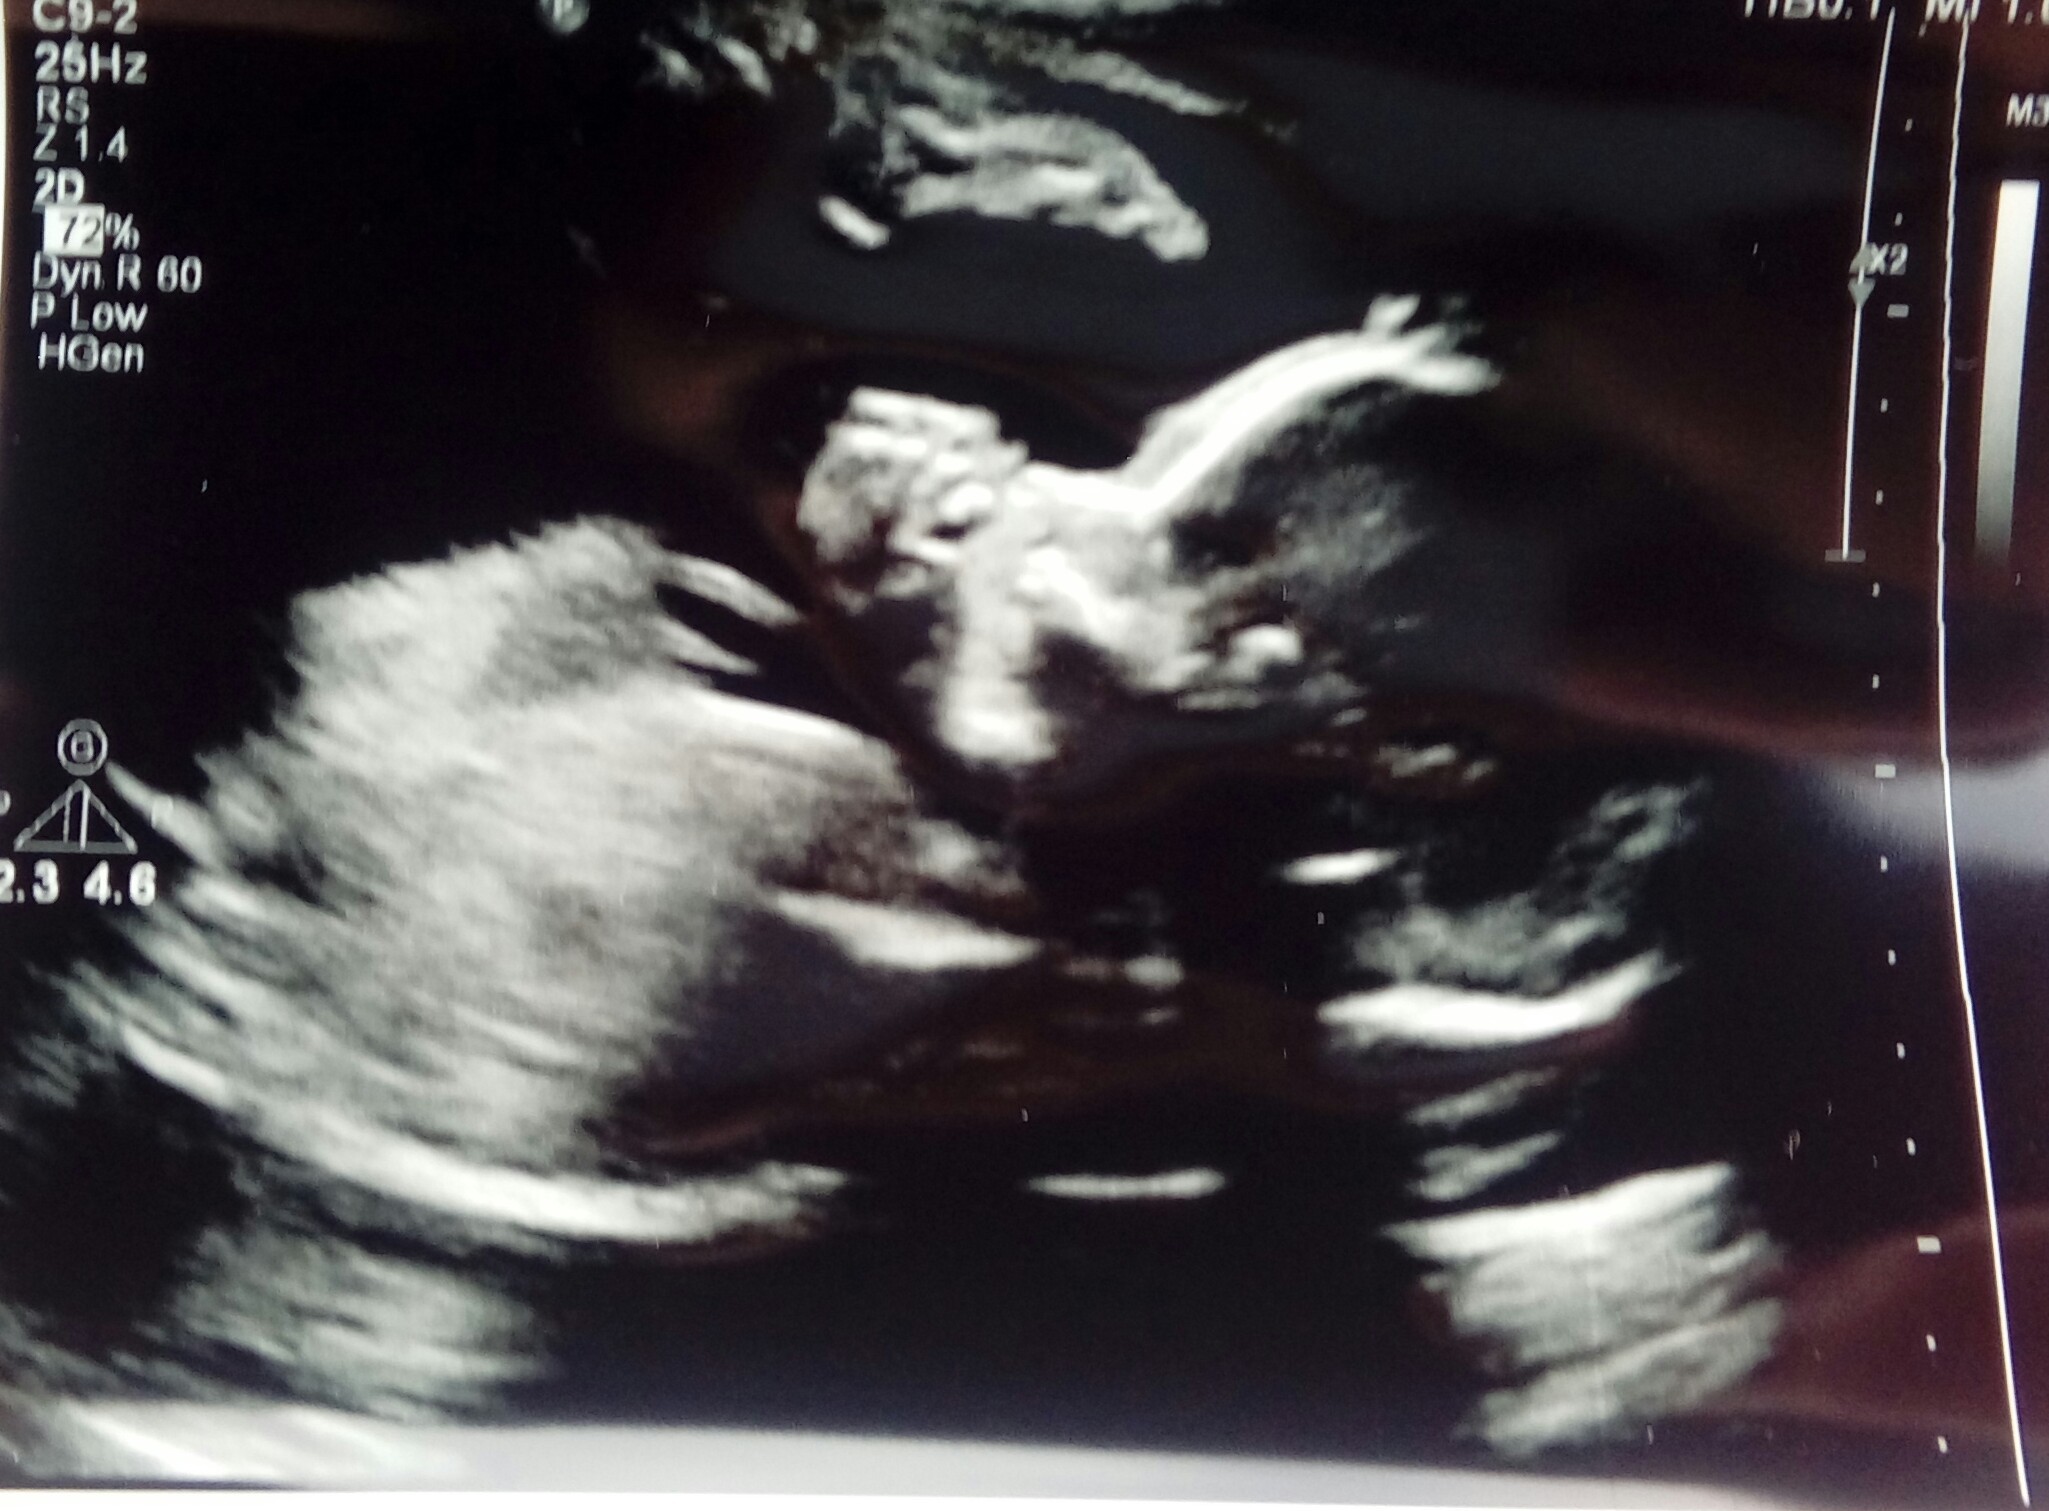

Czasem boję się, że się obudzę z tego snu, bo tylko na usg i potem na tych zdjęciach widzę, że to prawda.

Ja wczoraj mialam ostatnie badanie serduszka babelka:) skonczony 24 tc i ponoc juz nie ma ryzyka:) dr mowi ze tak jest z jej doświadczenia . dostalam piekne zdjecie siurasa i malo wyrazne ale jest jak ssie malenstwo kciuk.

• 20180814_141115.jpg

20180814_141115.jpg

673,8 KB · Wyświetleń: 91